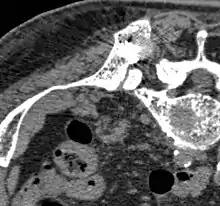

سیمان استخوانی (bone cement) ترکیبی شیمیایی است که در بدن انسان به منظور اتصال استخوان ها یا مفصل های مصنوعی به یک دیگر استفاده می شود. این ترکیبات که عموما از جنس سرامیک ها و پلیمر ها می باشند به صورت فراوان در عمل های ارتوپدی و استئوتومی(Osteotomy) کاربرد دارند.

در این گونه عمل ها مفصل یا استخوان معیوب را برداشته و با اندام جدید جایگزین می کنند، حین جایگزین کردن استخوان یا مفصل در آن حفره هایی ایجاد می کنند که سیمان را درون آن می ریزند و این سیمان بعد از مدتی به مانند چسب سفت شده و باعث جوش خوردن کامل استخوان ها به هم می شود.[1][2]